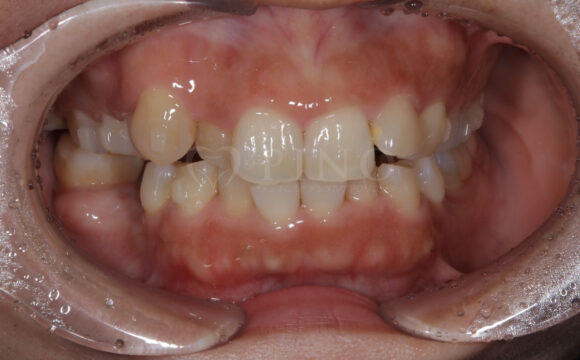

症例2:ワイヤー矯正後の後戻りが気になる(50代女性)

主訴 ワイヤー矯正後に後戻りが気になる 診断名 叢生 治療方法 マウスピース部分矯正 抜歯 なし オルソパルス なし 治療期間 10ヶ月 費用 436,000円+補綴費用360,000円 副作用・注意点 矯正後の後戻りを防ぐためリテーナーの使用が必要となる 備考 1年4ヶ月で補綴も完了した -